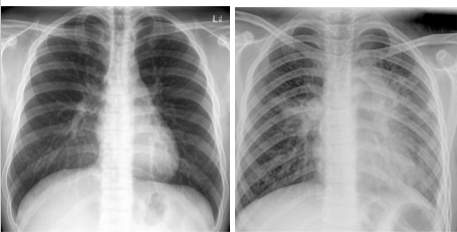

Differentiate which is PA vs AP view. Why

Left PA:

clavicles ELEVATED

medial border of scap NOT in center of lung fields

heart NOT magnified and enlarged

Right: AP

clavicles HORIZONTAL

scapulae in lung fields

heart appears magnified/elarged

labeled PA view